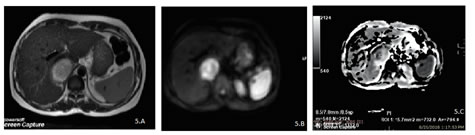

5

Figure 5-A, B, C: – A case diagnosed as benign neoplasm of right adrenal gland showing mildly hyperintense mass lesion in the right adrenal on axial T2eSSFSE sequence (A)with areas of diffusion restriction on DWI sequence (B) and corresponding areas of ADC reversal (C) with ADC value of 0.79x10-3mm2/s. On HPE, the case was confirmed to be adrenal adenoma.